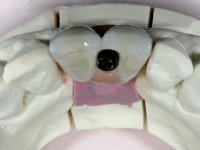

• Two months after implant placement and guided-bone regeneration, initiate the construction of a metal-ceramic fixed partial denture with two elements screwed on the dental implant.

With the implant osteo-integrated with did an impression (open-tray technique) and the dental technician started the construction of a gold framework. The use of an abutment made of a gold alloy allowed us to do a framework with a perfect fit.

During the framework try-in, the color survey was done in order to proceed with the ceramics placement, with a crown and gingiva-components.